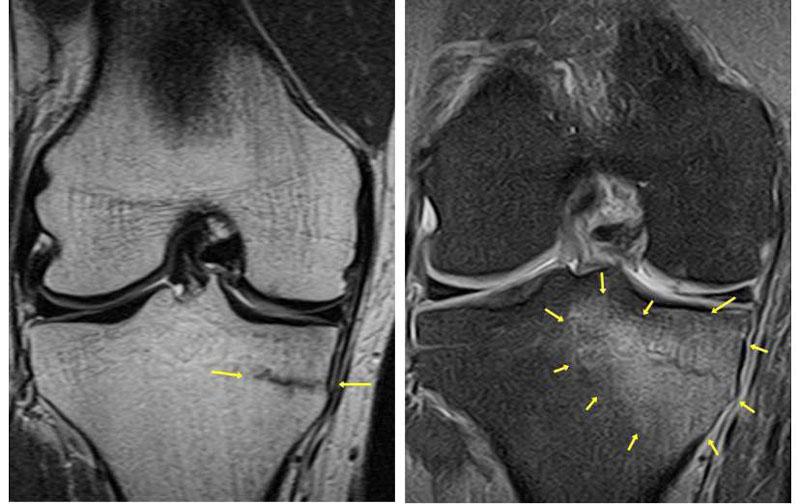

«К сожалению, так и случилось с одним из наших пациентов. После пробежки начал болеть коленный сустав, в связи с чем он обратился для прохождения магнитно-резонансной томографии. На изображениях врачи-рентгенологи увидели перелом, а вокруг него - зону отека костной ткани. Откуда этому взяться, если травмы, как таковой, не было? Дело в том, что под воздействием непривычно большой нагрузки балки костной ткани могут не выдержать и сломаться. Возникает так называемое стрессовое повреждение. Оно не приводит к смещению отломков, но сопровождается болью и, конечно, требует лечения», - объясняет Наталия Александровна. – «Желаем нашему пациенту скорейшего выздоровления, и напоминаем всем, решившим заняться спортом - увеличивать свою физическую активность можно и нужно».